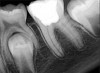

Figure 6. Preoperative radiograph of carious exposure on tooth No. 19. Courtesy of Dr. Mohammed A. Alharbi.

Figure 6

Case 1: Direct Pulp Cap

Figure 6 shows the preoperative radiograph of an apparent carious exposure on tooth No. 19 of a 20-year-old male patient. A diagnosis of reversible pulpitis was made based on the history and clinical exam. After anesthesia and caries removal, the exposure was seen (Figure 7) and covered with BC RRM-Fast Set (Figure 8). After the BC base had fully set, a bonded resin was placed and a postoperative radiograph taken (Figure 9). At the 6-month follow-up visit, the tooth was asymptomatic and tested vital. Radiographically, no signs of pathology were noted (Figure 10).